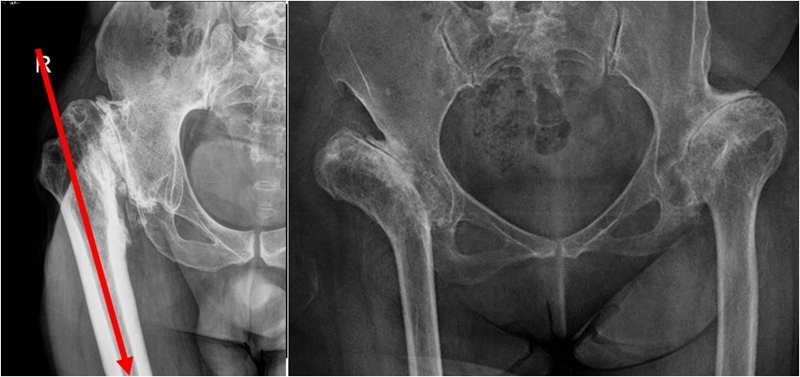

(3)股骨成角畸形

程度轻,且远离假体安放位置:近端固定短柄假体或小号骨水泥型假体。

严重且靠近假体安放位置:必须行截骨矫正,以获得良好的对线。

股骨截骨的不同方法:

股骨近端截骨重建——截骨方式:横形、斜形、阶梯式及双V形截骨

优点:不改变股骨近端的解剖,保持臀中肌附丽点完整,截骨后能矫正股骨的前倾角,是较为理想的股骨缩短方法。

缺点:①骨折——截骨两端捆钢丝;②截骨端不稳定,术后骨折不愈合——足够长的远端固定型非骨水泥型假体或组配型假体,假体长度足够,避免型号过小,必要时使用骨板加强固定;③失血多、时间长。